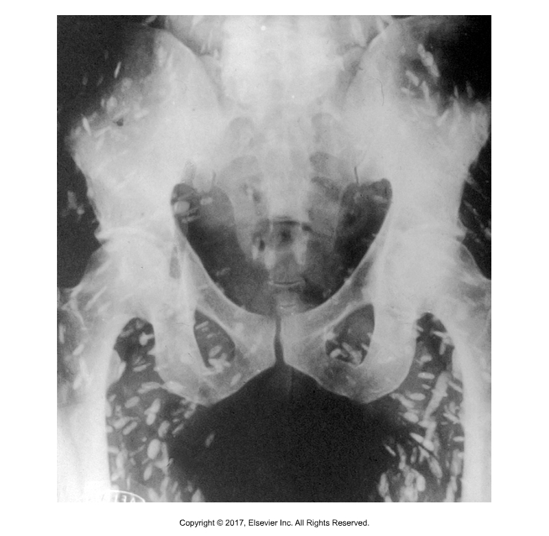

Echinococcus metacestode

Larval stage is hydatid cyst

E. granulosus forms unilocular cysts within liver, lung, other organs of ruminant

Thick cyst wall, thin germinal membrane; “Brood capsules” contain protoscolices that bud from germinal membrane; Each protoscolex forms one adult worm)